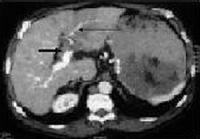

Foto 8: Tromboza de vena porta si transformare cavernoasa a venei porte la un pacient cu ciroza hepatica de etilogie alcoolica (sageata lunga indica vena splenica la jonctiunea cu vena mezenterica superioara, imediat inferior de tromboza, sageata scurta indica spre o forma serpigionoasa care indica transformarea cavernoasa a venei porte). |

Foto 9: Carcinom hepatocelular grefat pe o ciroya hepatica de etiologie alcoolica, complicat cu tromboza de vena porta (sageata scurta trombul cu o intrerupere brusca a traiectului portei, sageata lunga indica dezvoltarea circulatiei compensatorii). |